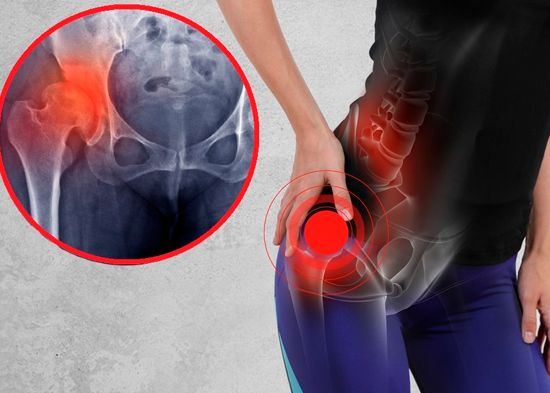

6 enfermedades autoinmunes que “atacan” más a la mujer y podrían debilitarla

A últimas fechas el sistema inmunológico ha cobrado tal relevancia que incluso se podría creer que antes su papel en el cuerpo humano era irrelevante. ¡Un gravísimo error! Y lo podemos apreciar no solo ante la llegada del covid-19 sino en las enfermedades autoinmunes, en las que por cierto las mujeres son más vulnerables.